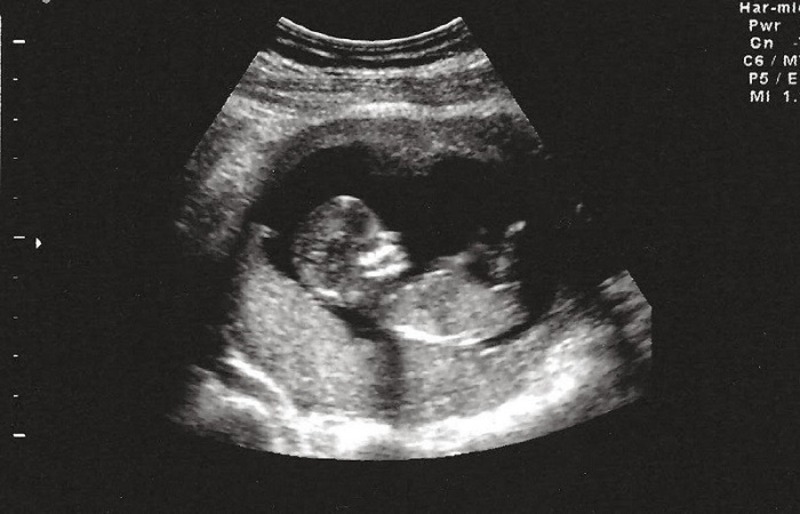

Siêu âm thai định kỳ là một phần không thể thiếu trong hành trình theo dõi sức khỏe mẹ và bé. Việc thực hiện đúng các mốc siêu âm thai nhi giúp phát hiện sớm dị tật, theo dõi sự phát triển và chuẩn bị tốt nhất cho quá trình sinh nở. Mẹ hãy cùng Mẹ Bầu Xứ Nghệ khám phá chi tiết từng mốc siêu âm quan trọng trong bài viết sau.

Siêu âm thai nhi định kỳ giúp theo dõi sự phát triển của thai và phát hiện sớm các bất thường, từ đó can thiệp kịp thời nếu cần. Đây là một phần quan trọng trong chăm sóc thai kỳ để đảm bảo sức khỏe cho cả mẹ và bé.

Trong suốt thai kỳ, có những mốc siêu âm quan trọng mà mẹ bầu cần thực hiện đúng thời điểm để theo dõi sự phát triển và sức khỏe của thai nhi. Mỗi giai đoạn đều có mục tiêu kiểm tra riêng, giúp phát hiện sớm các bất thường và chuẩn bị tốt nhất cho hành trình làm mẹ.